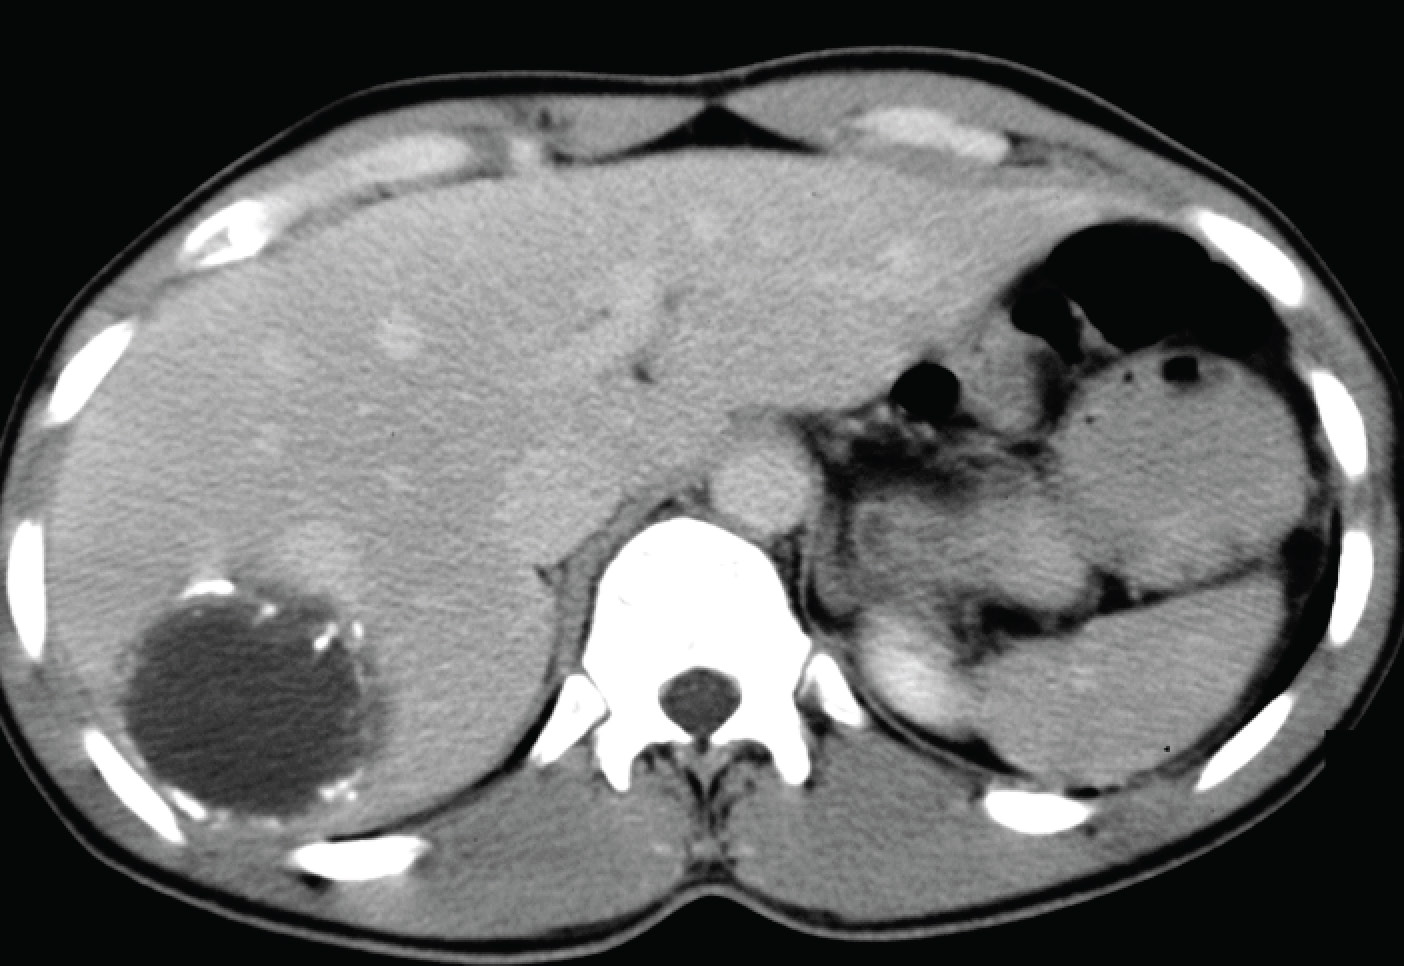

There is a calcified cyst just below the right hemi-diaphragm. Given the location of the lesion, the question of an infectious disease, and the scope of the patient’s travels, it is likely to be a hydatid cyst. The corresponding CT image is shown below.

Hydatid cysts are the embryonal stages of the dog tapeworm, Echinococcus granulosus. The organism is present worldwide, particularly in sheep-farming areas of the world, although it is not endemic in Singapore or the U.S. Hydatid cysts are generally asymptomatic until they become too big (growing at approximately 1 cm per year), rupture (usually from trauma) or compress critical structures. When calcifications are seen, the hydatid cyst in question is dying (or dead). The cyst can be removed as a whole via surgery – it is important not to rupture the cyst during surgery otherwise an intense allergic/inflammatory response will occur with the spillage of cyst contents into the liver/peritoneum). Experienced radiologists may also perform PAIR (percutaneous aspiration, injection – usually of alcohol or some other sclerosant – and re-aspiration to collapse the cyst) as a less invasive but equally effective treatment of hydatid cysts. But PAIR is not routinely performed with calcified cysts.